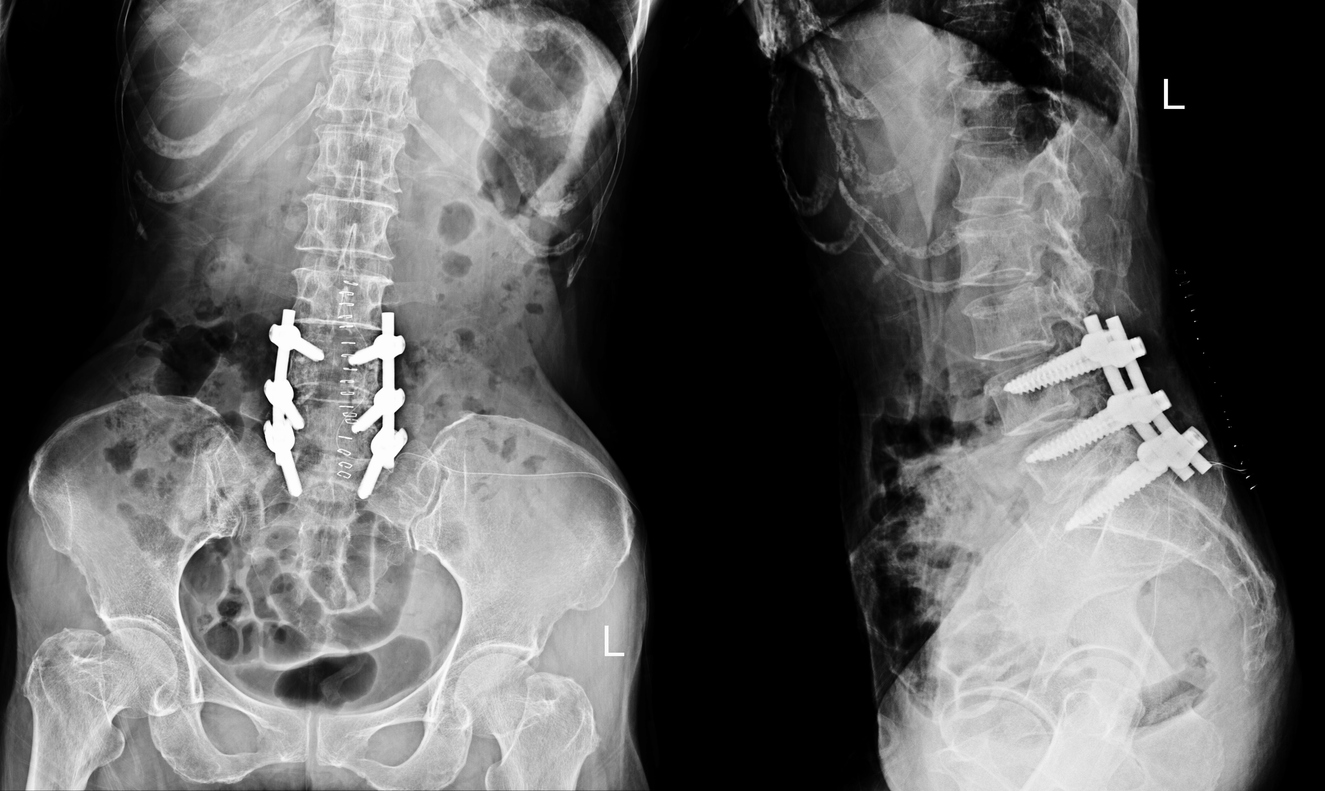

During a posterior lumbar interbody fusion (PLIF) or transforaminal lumbar interbody fusion (TLIF), Dr. Kazarian accesses the spine from an incision in the lower back. The damaged disc material is carefully removed from between the affected vertebrae, and a spacer (called an interbody cage) filled with bone graft material is placed in the disc space to restore proper height and alignment. Screws and rods are then secured to the vertebrae above and below to hold everything in position while the bone graft gradually fuses the vertebrae into a single, solid segment. Over time, new bone grows through and around the graft, creating a permanent biological bond.

Images & Diagrams

You will be carefully positioned face-down on a specialized surgical table. Dr. Kazarian will make an incision along the midline of your lower back over the affected vertebrae. The muscles are gently moved aside to expose the spine. The damaged disc is removed, any bone spurs or tissue compressing the nerves are cleared, and an interbody cage packed with bone graft is placed into the disc space. Titanium screws are inserted into the vertebrae above and below, and connecting rods are secured to stabilize the segment. The procedure typically takes two to four hours depending on the number of levels being fused and the complexity of your condition.